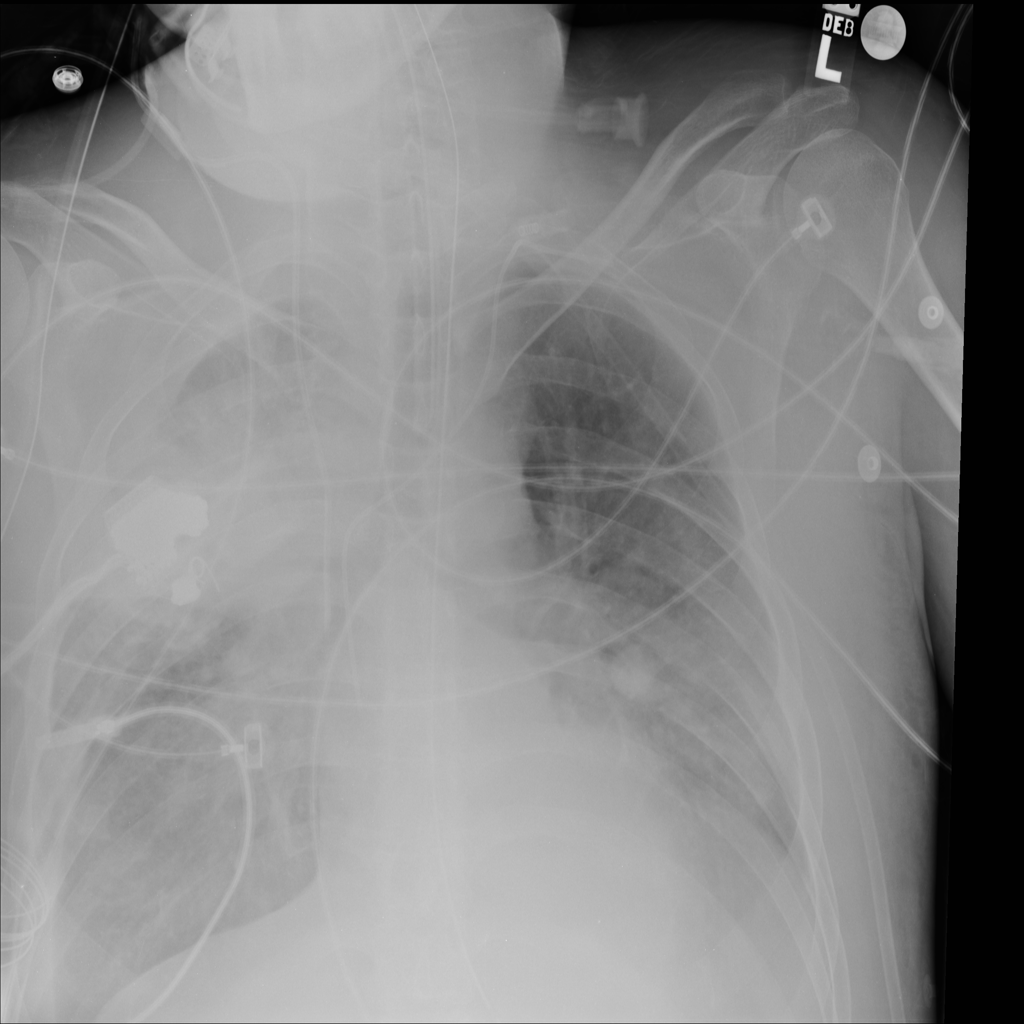

PAT-C1A7 · IMG-004Consolidation

PAT-C1A7 · IMG-004

PA